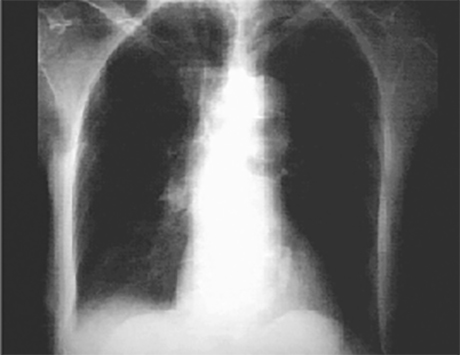

PA view

In this overpenetrated PA view, the calcified mitral valve annulus is demonstrated curvilinear density adjacent to the thoracic spine and within the cardiovascular silouette.